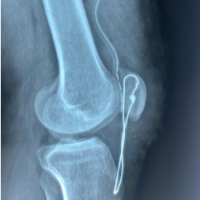

Considering that the ruptured tendon due to bone avulsion did not escape to the proximal A4 pulley, only a distal incision was made at first. However, after exploration, it was determined that the A4 pulley was ruptured and the tendon was advancing proximally. Then, a mini-incision was made over the A1 pulley. The ruptured tendon was found at the proximal border of the A1 pulley (Fig. 2). The tendon was identified, mobilized, and delivered distally through the pulley system using a silicone rod to avoid damaging the intact pulleys and to facilitate gliding (Fig. 3). After preparing the FDP insertion site in the distal phalanx, the tendon was fixed using a 2.5 mm mini anchor suture (Fig. 4). Since the tendon tension was appropriate, no lengthening procedure was considered for the tendon (Fig. 5). The A4 pulley was repaired with 4/0 surgical suture. The flexor tendon sheath and skin were meticulously closed.

Figure 4: Confirmation of anchor placement with fluoroscopy.

Figure 5: Demonstration of pre-operative and post-operative tendon tension.